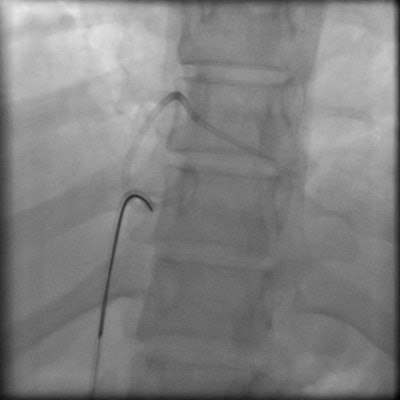

Percutaneous retrieval of the retained fragment of the fractured portacath catheter was successfully accomplished on the second attempt. Following prepping of the right groin, the right femoral vein was punctured and an 8 French sheath was inserted. Selective catheterization of the right ventricle was performed using a 6 French catheter. A 25-mm snare was used to capture the migrated retained fragment. It was then removed successfully without immediate complications.

Percutaneous transcatheter retrieval of the portacath fractured fragment by interventional endovascular techniques is the preferred method of management. GooseNeck loop snare, which we have used in this case, is the most popular device used with a success rate of about 90%.4 If the fractured fragment that has migrated to the heart is not detected and removed early, it becomes endothelialized and may require surgical removal.10